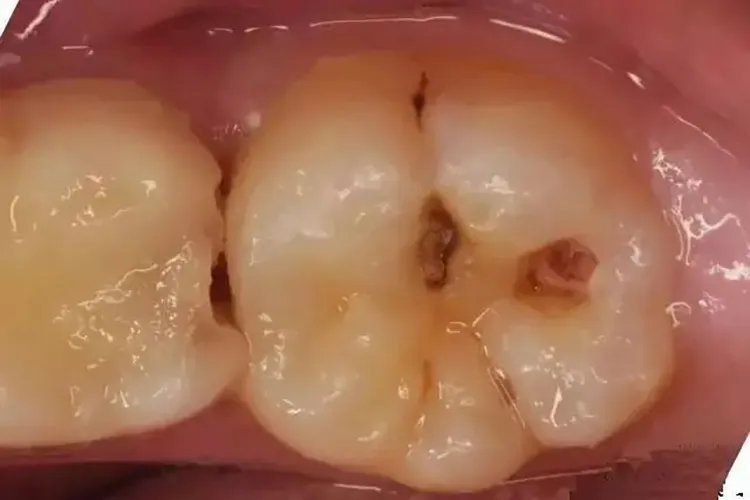

概述蛀牙又称为龋病,是一种牙体硬组织慢性进行性破坏疾病。龋病可分为浅龋、中龋、深龋三种类型,具有不同的临床表现。龋病是由于细菌等多种因素共同作用导致的。症状浅龋发生在牙冠为牙釉质龋,又分为窝沟龋和平滑面龋;发生在牙颈部或者牙根表面的为牙骨质龋或者牙本质龋。浅龋临床表现为窝沟龋的龋损部位变黑,平滑面龋一般呈白垩色,黄褐色或褐色斑点,多无龋洞形成,用探针检查时有粗糙感或能钩住探针尖端。

中龋病变已到达牙本质浅层,龋损部位牙本质呈黄褐或深褐色;龋洞形成,牙体缺损明显;病变牙本质质地较软;X线片检查显示牙体组织低密度影累及牙本质浅层。

深龋表现为龋洞深大,达牙本质深层,龋损部位牙本质呈黄褐或深褐色;龋洞形成,牙体缺损明显;病变牙本质质地较软;当食物嵌塞入龋洞中或患牙遇冷、热、酸、甜、化学刺激时可出现疼痛。X线片检查提示牙体组织低密度影累及牙本质深层。位于邻面的深龋,牙的外观略有色泽改变,洞口较小而病损破坏很深,容易漏诊。病因龋病是人体较常见的一种疾病,主要病因是口腔内的致龋微生物。致龋微生物有很多种类,一般比较常见的微生物,比如链球菌、放线菌以及乳酸杆菌类,被称为致龋菌。饮食因素如碳水化合物的种类以及摄入的量、摄入的频率等,也是引起龋病的重要因素。另外,如果食物在牙缝隙内停留时间较久,未及时清理,也会引起龋病。诊断根据牙齿的外观和主诉症状可诊断龋齿。X线可以发现隐藏的和肉眼难以看见的龋齿,可以显示龋洞侵入牙齿的深度。治疗化学疗法用化学药物处理龋损,终止或消除病变。再矿化治疗采用人工方法使已脱矿、变软的釉质或牙骨质发生再矿化,恢复硬度,终止或消除早期龋损。预防性树脂充采用窝沟封闭剂防治窝沟龋,适用于窝沟内微小浅龋及可疑龋。修复性治疗手术去除龋坏组织,制成一定洞形,选用适宜的修复材料修复的缺损部分,恢复患牙的形态和功能。